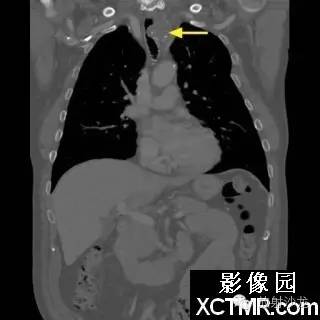

On the contrast-enhanced CT of the chest, there is a heterogeneous mass arising from the left lateral wall of the trachea. The mass demonstrates extratracheal extension as well as extension into the tracheal lumen. (Figure 1 and Figure 2). The mass also contains internal calcifications (arrows), representing chondroid matrix mineralization (Figure 3 and Figure 4).

胸部增强扫描示气管左侧壁发出一不均质的肿块影,肿块向气管内外扩展(图1、2)。其内可见钙化影(箭头),代表软骨基质的钙化(图3、4)。